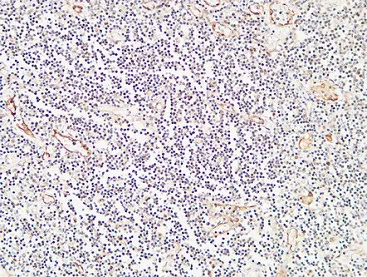

CD83 Rabbit Polyclonal Antibody

Cat: APRab08469

CD19 Rabbit Polyclonal Antibody

Cat: APRab08256